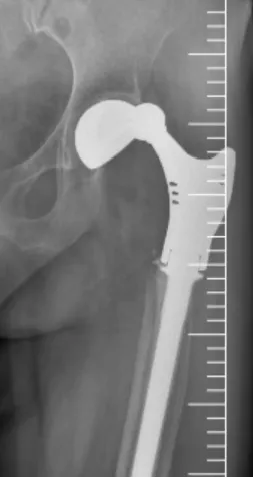

接诊后,北京积水潭医院郑州医院骨病与骨肿瘤科主任秦光华团队展开全面评估,影像学检查显示多重棘手问题:

人工髋关节脱位明确且假体松动明显,

患侧脱位后解剖结构紊乱,进一步增加治疗难度。

在神经电生理监测全程保障下,手术期间未出现任何并发症,假体位置良好、固定牢固,手术圆满成功。

术后复查显示,张先生的人工髋关节位置正常,假体固定稳定,骨缺损修复效果符合预期,未出现感染、出血等并发症。后续将在康复团队指导下进行进一步功能训练。